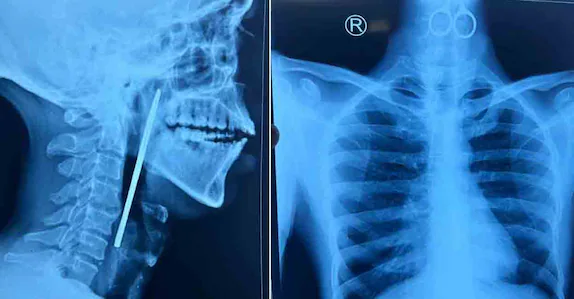

അന്നനാളത്തിൽ കത്രിക കുടുങ്ങി കിടക്കുന്നതായി എക്സറേ പരിശോധനയിൽ കണ്ടെത്തി. തുടർന്ന് രോഗിയെ ഇഎൻടി വിഭാഗത്തിൽ പ്രവേശിപ്പിച്ചു.

തിങ്കളാഴ്ച രാത്രി നടത്തിയ അടിയന്തിര ശസ്ത്രക്രിയയിലൂടെയാണ് 15 സെന്റിമീറ്ററോളം നീളമുള്ള കത്രിക പുറത്തെടുത്തത്. ഇഎൻടി വിഭാഗത്തിലെ ഡോ. ശ്രീജിത്ത്, ഡോ. നിഖിൽ, ഡോ. ചിത്ര, ഡോ. ഫാത്തിമ, ഡോ. ആഷ്, അനസ്തീസിയ വിഭാഗത്തിലെ ഡോ. മിനു, ഡോ. ധന്യ, ഡോ. ഫഹ്മിദ, ഡോ. രാഗിൻ എന്നിവരാണ ശസ്ത്രക്രിയ സംഘത്തിലുണ്ടായിരുന്നത്. രോഗിയുടെ ആരോഗ്യനില തൃപ്തികരമാണെന്ന് ആശുപത്രി അധികൃതർ പറഞ്ഞു.